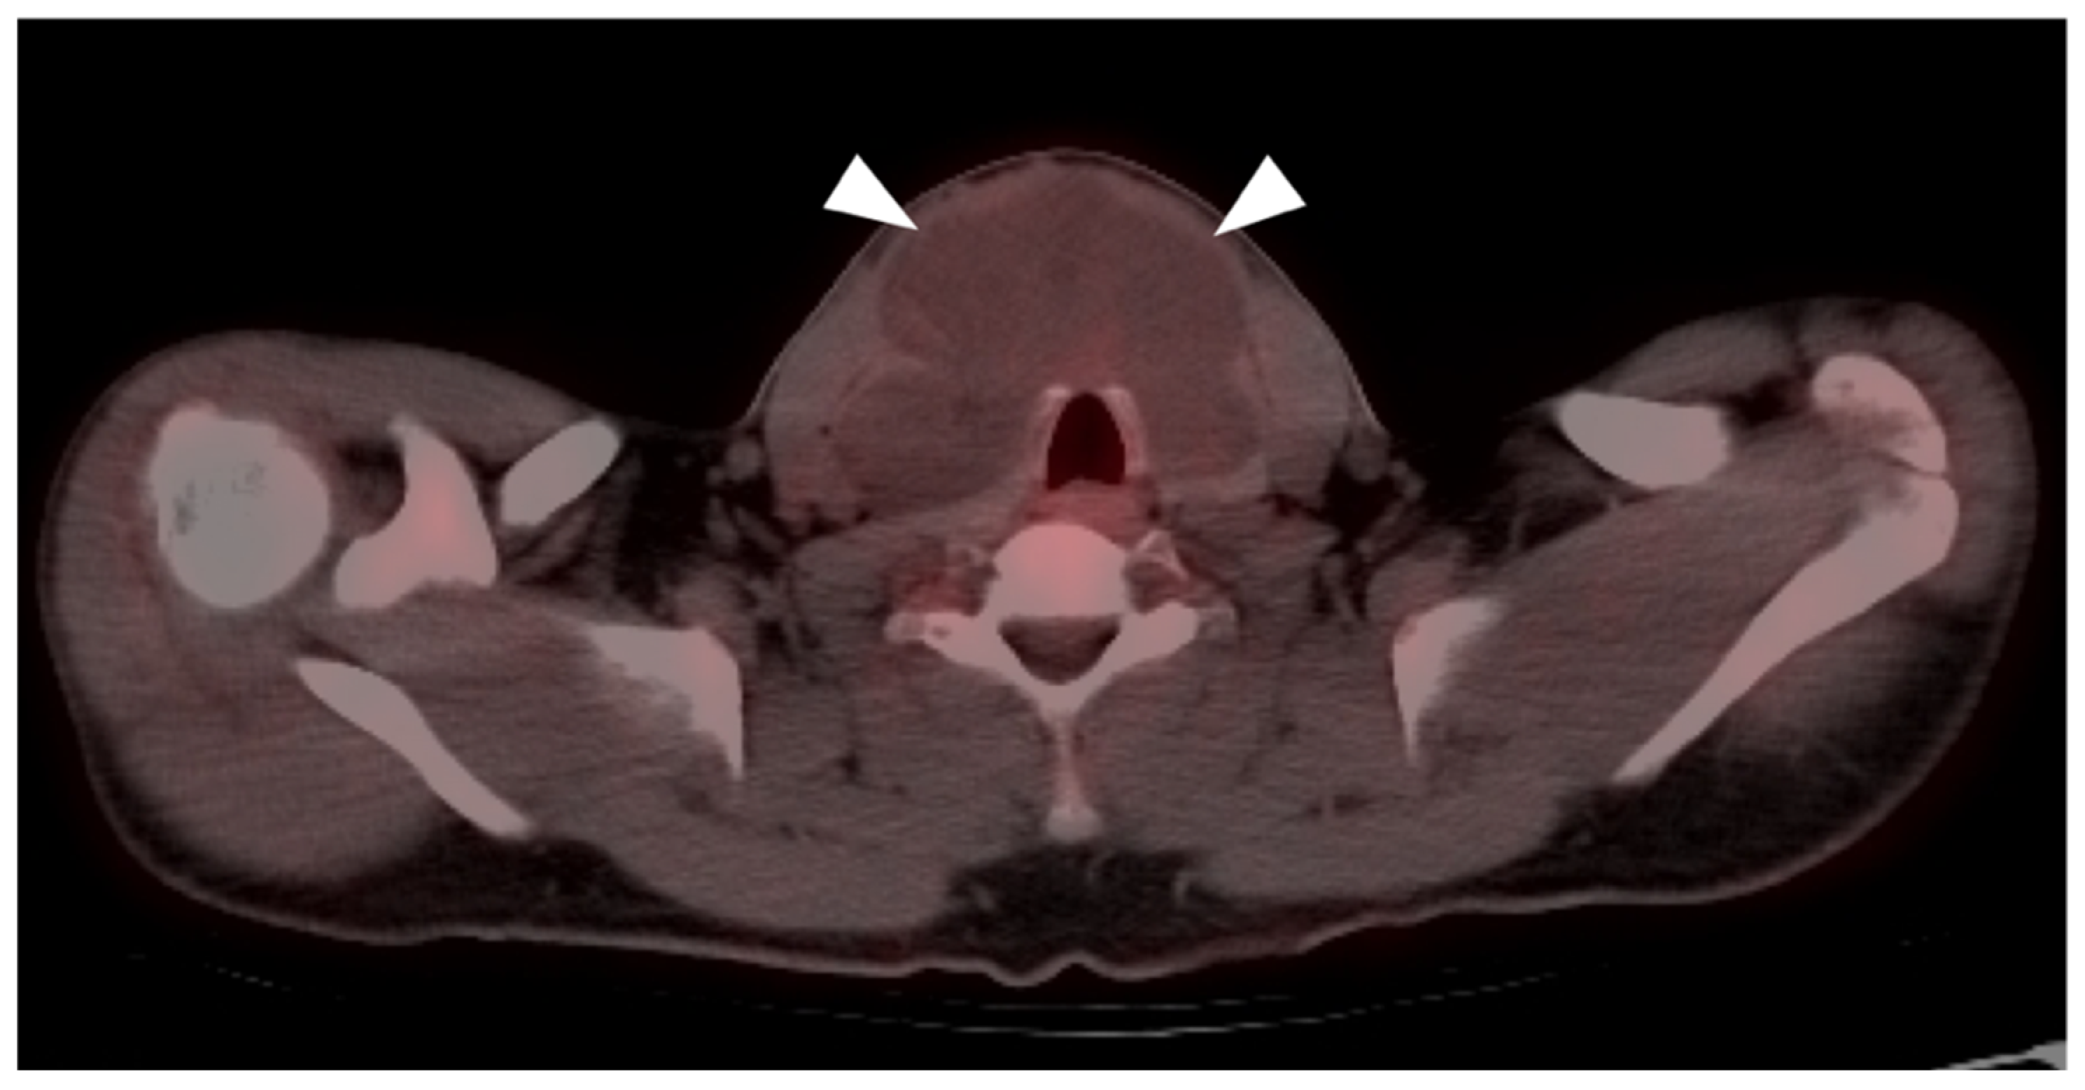

3. Sarcomas

3.1. Soft Tissue Sarcomas

3.2. Bone Sarcomas